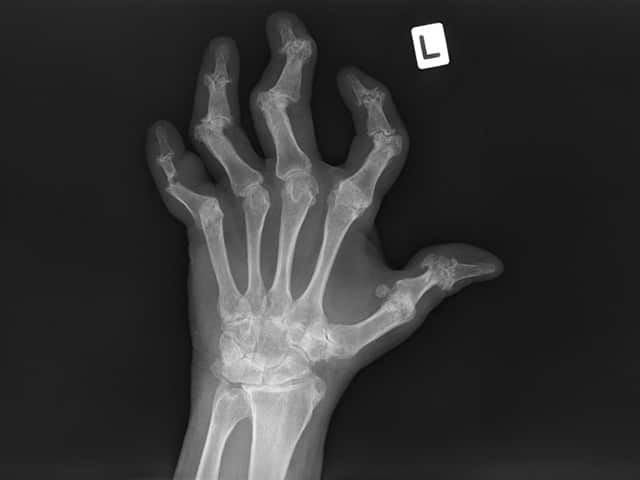

X-ray findings that are characteristic of psoriatic arthritis include:

Left hand